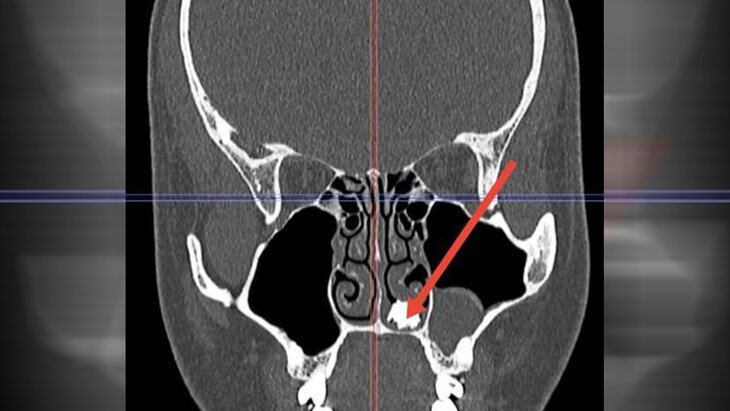

Врачи Долгопрудненской больницы извлекли из носа 22-летнего молодого человека молочный зуб. Об этом сообщила пресс-служба подмосковного Минздрава.

По информации ведомства, пациент поступил в медучреждение с жалобами на продолжительный насморк. Проведенная диагностика выявила в полости носа образование костной плотности, в связи с чем потребовалась операция.

Во время хирургического вмешательства был извлечен неизвестно как попавший и неизвестно сколько пролежавший в носовой полости покрытый грибковым содержимым молочный зуб, рассказала заместитель главврача больницы по хирургии Евгений Кутырева.